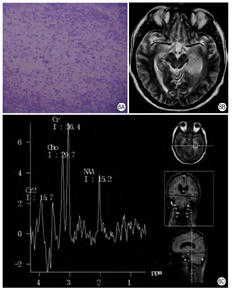

病理改变:PML病理表现为少突神经细胞受到乳多空病毒的选择性破坏,引起脱髓鞘。脑白质内有多灶性损害,形成脱髓鞘融合区,大脑半球比小脑易于受累,特别是皮质下灰、白质交界处。尸解见脑白质有颗粒状黄色软化灶,弥漫而不对称,融合的病灶可达数厘米。组织病理学所见在多灶性脱髓鞘区周围有深染的少突胶质细胞,具毛玻璃样外观,其核肿胀,内含嗜酸性无定型的病毒包涵体,透射电镜上病毒呈结晶状排列,大小为33~39 nm;见巨大畸形的星形细胞,具有多形性分叶状核(图6A),常呈怪形。有大量泡沫状巨噬细胞,以及组织坏死。

影像表现:大脑白质有广泛多发脱髓鞘改变,呈散在不对称性分布,小脑、脑干与脊髓病变比较少见。白质内病灶为多发性,分布不对称,常见多灶性低密度区,呈圆形或椭圆形。注射对比剂后通常无增强反应及肿块影,有时轻度占位效应及强化反应,偶尔累及灰质并引起占位效应。MR T1WI为阴性,或显示低信号病灶,T2WI白质区出现均匀的高信号病灶(图6B),边界清楚,无占位效应,亦无特异性[9]。常为多发性和不对称性,一般无明显占位表现。MR波谱表现为Cr升高,NAA减低(图6C),复查时可见病变进行性加重,小病灶也可逐渐融合扩大,晚期出现脑萎缩改变。近来,有学者研究,MT MRI上,PML病灶磁化转移率低,而HIV相关的白质病变磁化转移率仅轻度降低,可以用来鉴别PML病灶与HIV相关的白质病变[10]。

病理改变:结核病典型变现是结核结节与干酪坏死,结核结节有上皮细胞和郎罕氏细胞(Langhans cells)构成,中心可见干酪坏死,周围有纤维母细胞和淋巴细胞,多累及脑膜,也可累及脑实质,形成占位。脑脊液检查可查到结核菌(图8A)。

影像表现:如果累及脑膜,多发生脑基底部脑膜增厚渗出,MRI增强可见明显异常强化。如果累及脑实质,在脑内可形成多发的类圆形结节,MRI呈长T1长T2信号,周围水肿明显,也呈长T1长T2信号,也可见周围水肿不明显的结节灶[13](图8B,图8C,图8D)。因AIDS免疫力低下,进展迅速,预后欠佳。